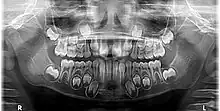

La dentición decidua, conocida también como dentición de leche, dentición temporal, dentición primaria, o dientes mamones,[1] es el primer juego de dientes que aparecen durante la ontogenia de humanos y como en las de otros mamíferos. Se desarrollan durante el periodo embrionario y se hacen visibles (erupción dentaria) en la boca durante la infancia. Son generalmente sustituidos, tras su caída, por dientes permanentes, aunque, en ausencia de ésta, pueden conservarse y mantener su función algunos años. En todos los mamíferos, salvo algunas excepciones, se recambian solo incisivos, caninos y premolares, apareciendo los molares ya como parte de la serie dentaria definitiva; este tipo de reemplazo se denomina hemifiodoncia.[2]

En la dentición temporal hay 20 dientes en total: 8 incisivos, 4 caninos y 8 molares temporales.